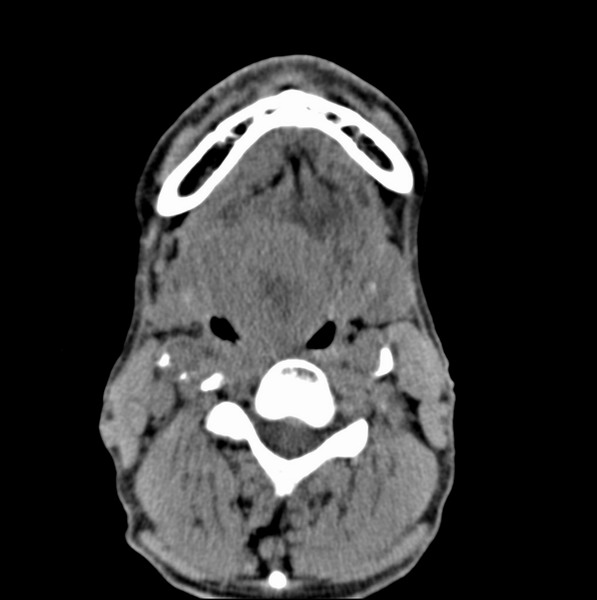

标题: CT19620:舌根肿物

男、60、舌根肿物。

舌垂直肌和横肌影处肿块影,边缘不规则,咽腭扁桃体及舌下间隙脂肪影消失,病变侵及口咽。

考虑-----舌根癌

舌跟软组织肿块,较大有坏死,钙化。结合年龄一般是恶性肿瘤。

舌根部较大软组织肿块,其内见坏死低密度区及钙化影;考虑舌根癌可能。